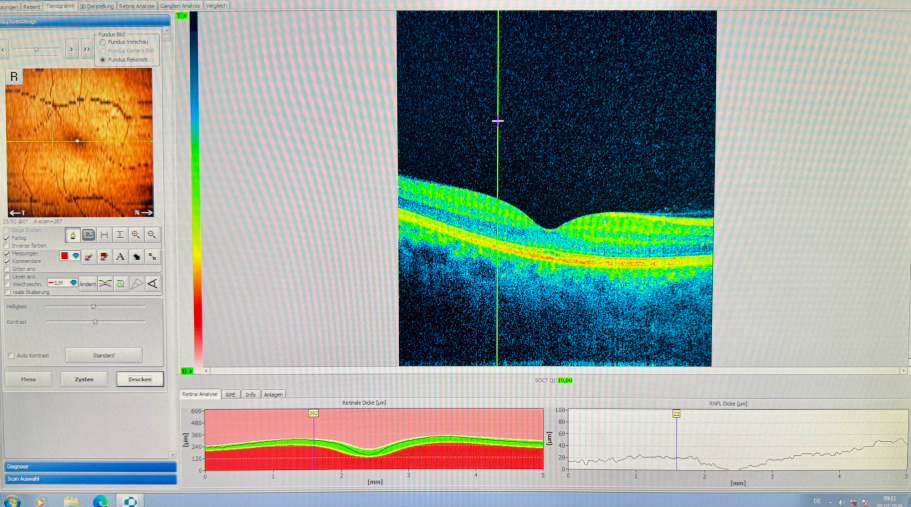

OCT